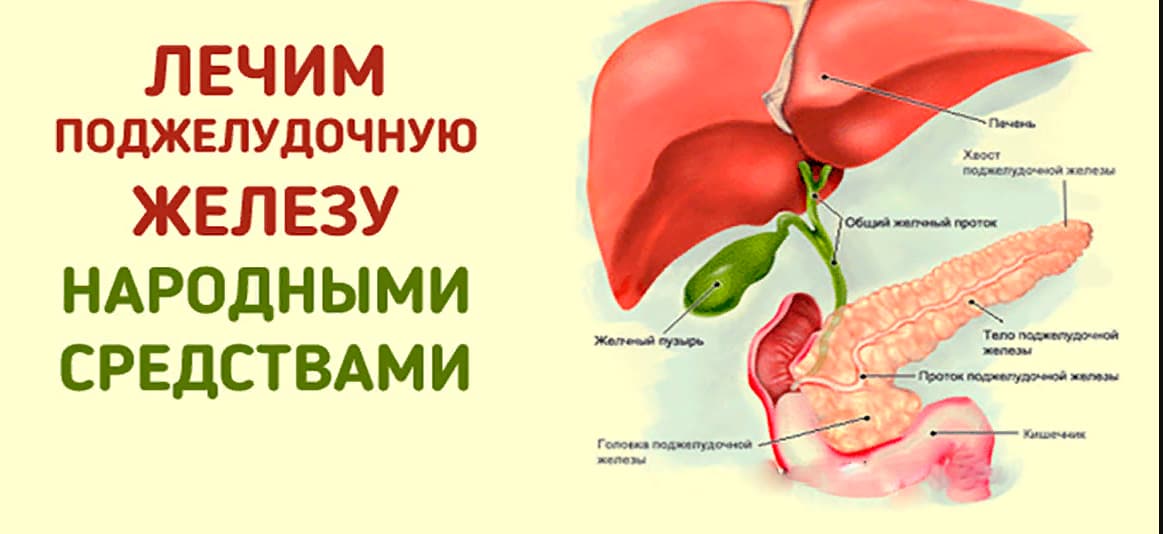

Анатомическое расположение поджелудочной железы

ПЖ располагается в брюшной полости, ближе к I–II позвонкам поясничного отдела позвоночника. Орган плотно крепится на задней стенке желудка, а 12-перстная кишка окружает ее, поддерживая в необходимом положении.

Параметры ПЖ взрослого человека в норме должны быть 20-25 см, вес – 70-80 граммов.

По анатомическому строению орган делится на 3 составных части: это головка, тело и хвост. Головкой ПЖ обращена к желчному протоку, тело находится за желудком, ближе к его нижней части. Рядом с телом в норме располагается поперечно-ободочная кишка. Хвостом ПЖ обращена к селезенке, и уходит к левому подреберью. По отношению к пупку, со стороны брюшной стенки, ПЖ расположена над ним, на 5-10 см выше.

Надо знать, где находится поджелудочная железа у человека, чтобы отличить боли от симптомов других патологий внутренних органов.

Рецепты народных целителей

Фитотерапевты и целители предлагают лечение травами для поддержания ПЖ в период ремиссии. Такие рецепты рекомендуют и терапевты, гастроэнтерологи, когда у пациента наступает стадия ремиссии и его выписывают на домашнее долечивание.

Даже если человек после больничного лечения едет в профильный санаторий, там врач обязательно назначит пить лекарственные настои, каждому человеку по своей схеме. Но можно готовить настои, отвары дома, самостоятельно, прежде получив консультацию своего лечащего врача.

Все рецепты предполагают соединение нескольких лекарственных растений. Поэтому предварительно следует проверить, не будет ли аллергии на какой-то компонент.

Избавиться от воспаления ПЖ навсегда при соблюдении диеты, использования лечения травами, практически невозможно.